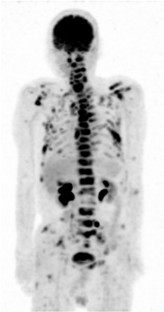

Gallbladder cancer is often diagnosed with metastasis and is known to have poor prognosis. Although, gallbladder cancer often metastasizes to liver, lung, or lymph nodes, metastasis to gastrointestinal tract is not common. Several autopsy studies reported colorectal metastasis from gallbladder cancer, but most of these cases were supposed to be gastrointestinal invasion from peritoneal dissemination. We experienced a rare case of hematogenous colon metastasis from gallbladder cancer. Colonoscopy for a 76-year-old man who was diagnosed as gallbladder cancer revealed two 5-mm flatly elevated lesions with central erosion in the transverse and sigmoid colon. Endoscopic mucosal resection (EMR) revealed poorly differentiated adenocarcinoma in hematoxylin and eosin staining. Additional immunohistochemistry examination showed strongly positive CK7 expression with negative CDX2, and suggested colon metastases from gallbladder cancer. Despite the positive vertical margin in EMR specimens, autopsy finding denied colorectal invasion from peritoneal dissemination and proved vascular spread colon metastases. Gastrointestinal metastasis is often misdiagnosed as a primary tumor, and thus, it is important to recognize gallbladder cancer as a potential origin of gastrointestinal metastasis.

• Bone metastasis